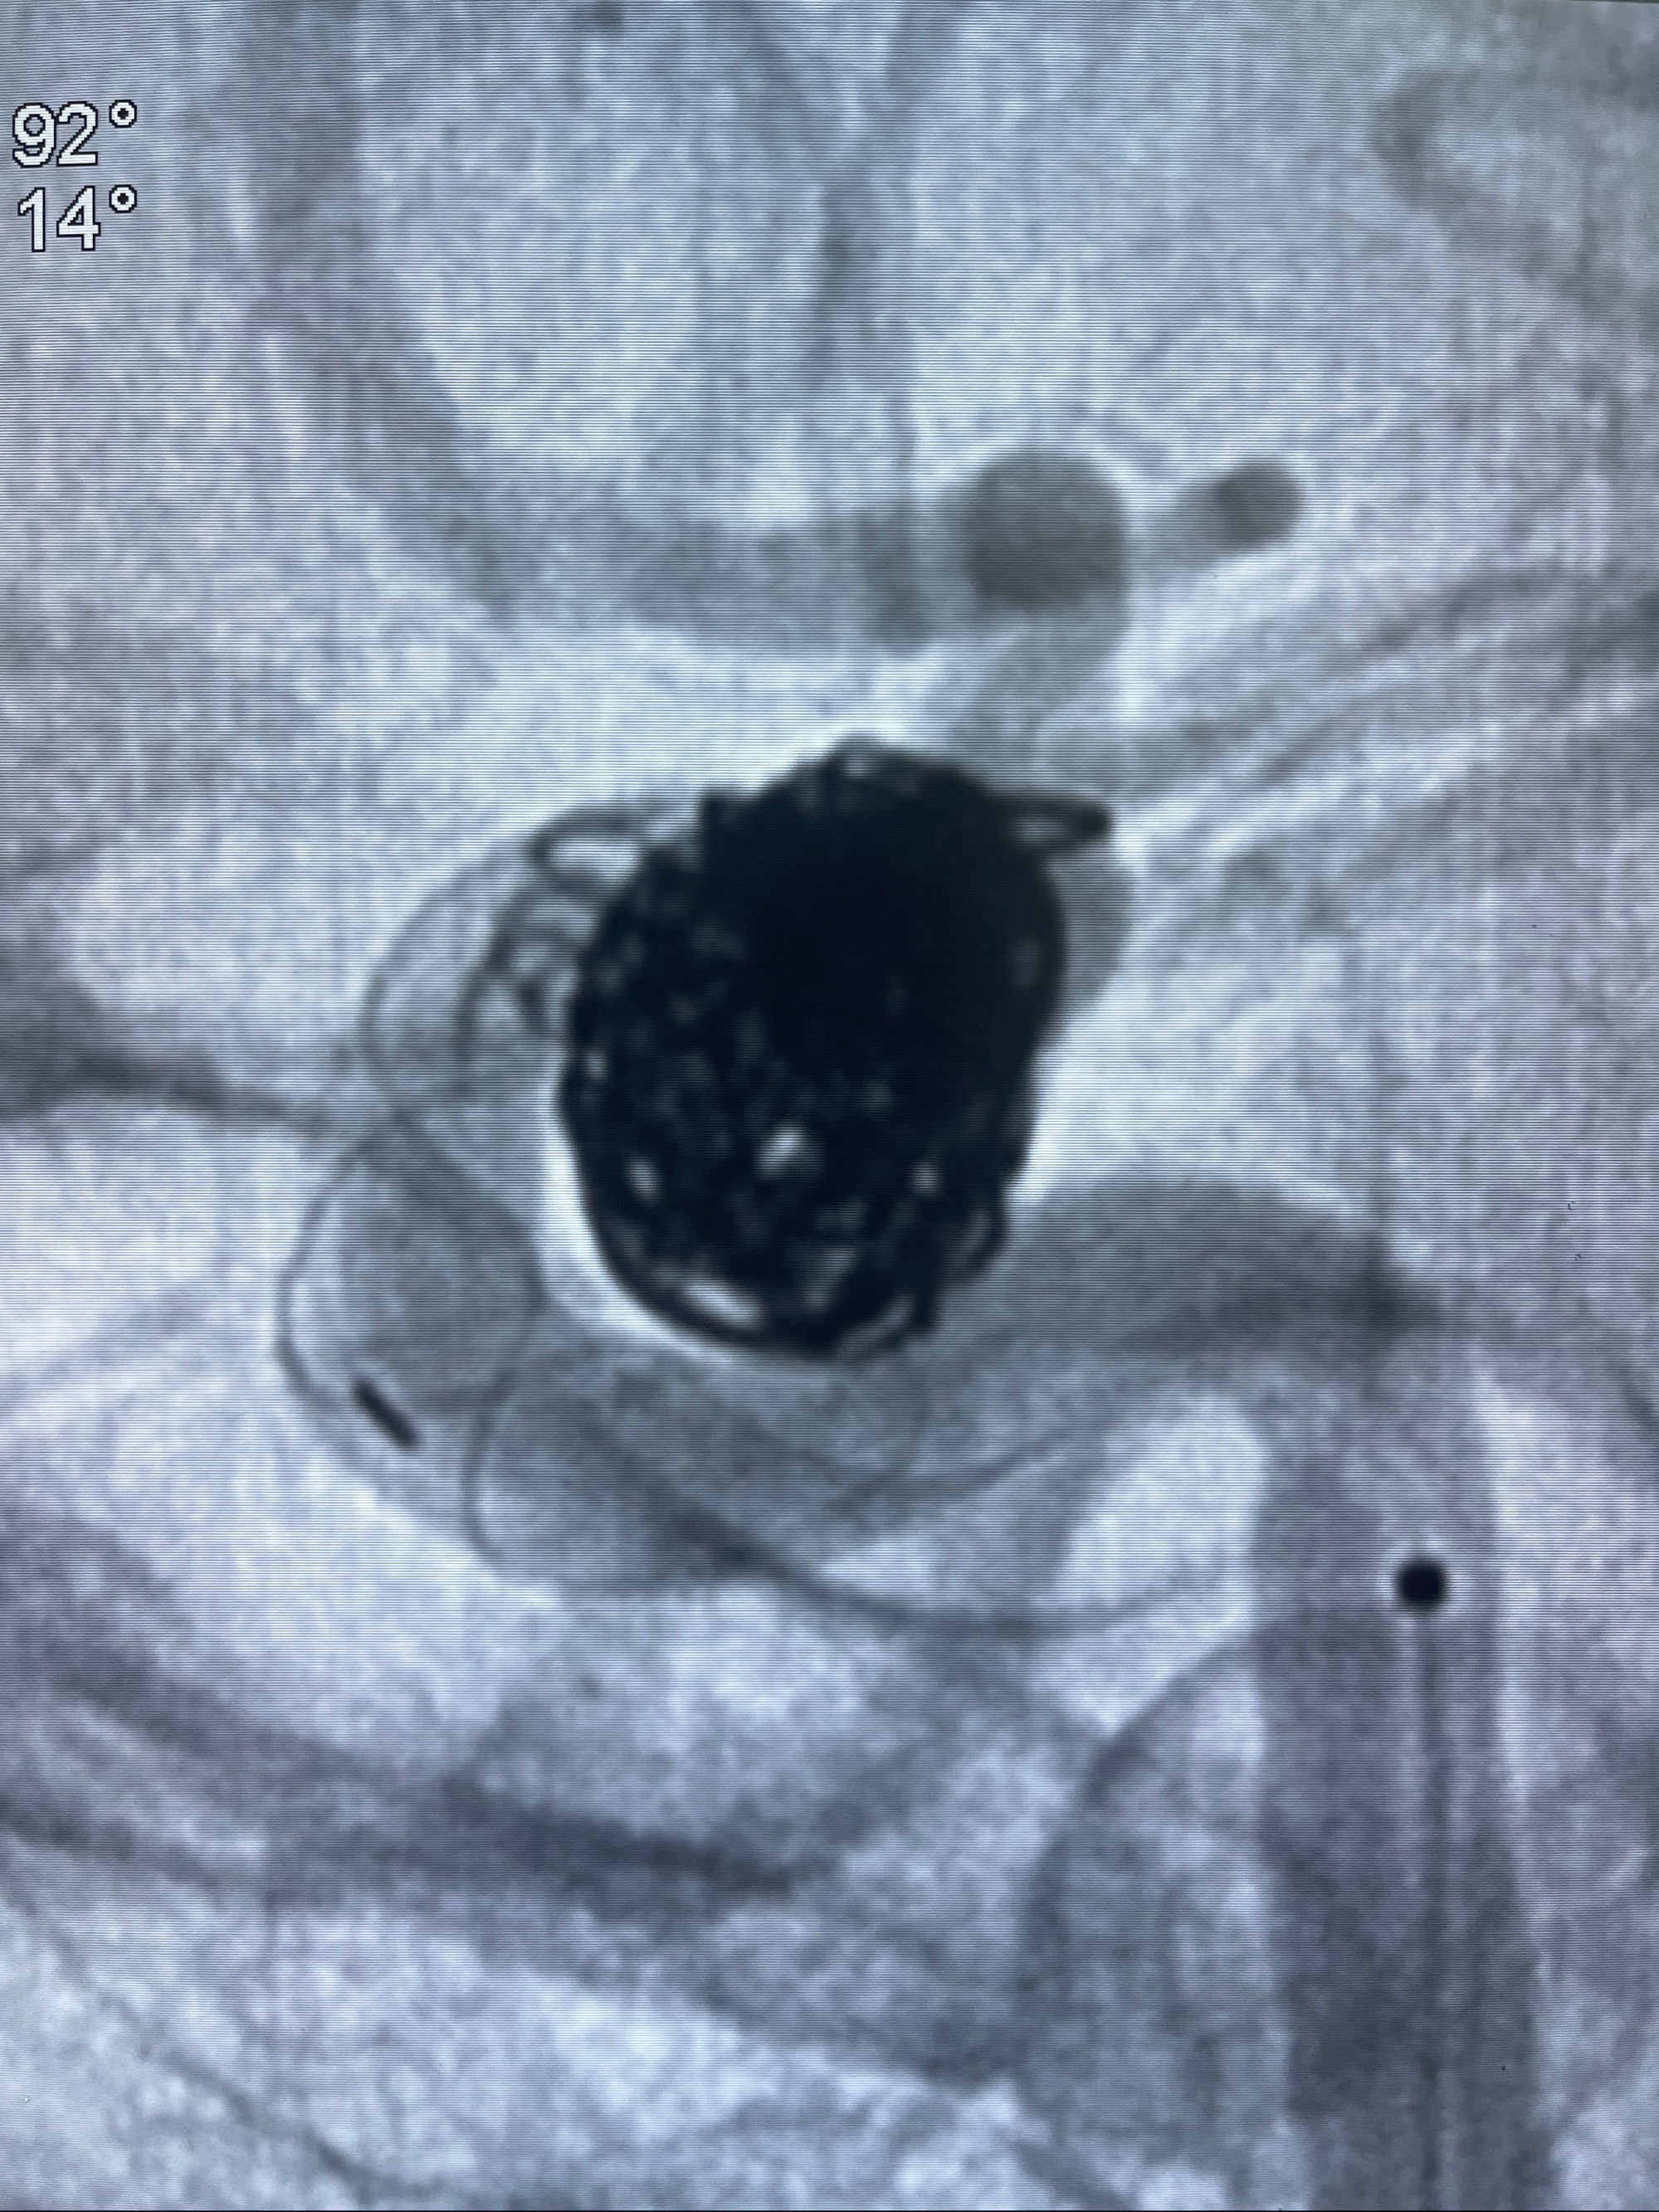

2023-08-30DSA:左侧颈内动脉眼动脉动脉瘤,约3*9.2*7.3mm大小

密网支架辅助栓塞

- Tubridge 4.0-20mm密网支架

- 加奇微弹簧圈:7*30/6*20/5*20/2*8

术后3D显示支架贴壁佳